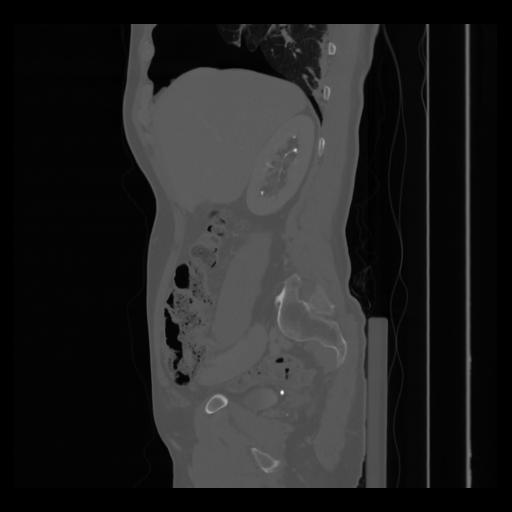

36 CUERPO,CE,Sagittal,3.000,CUERPO,Sagittal,